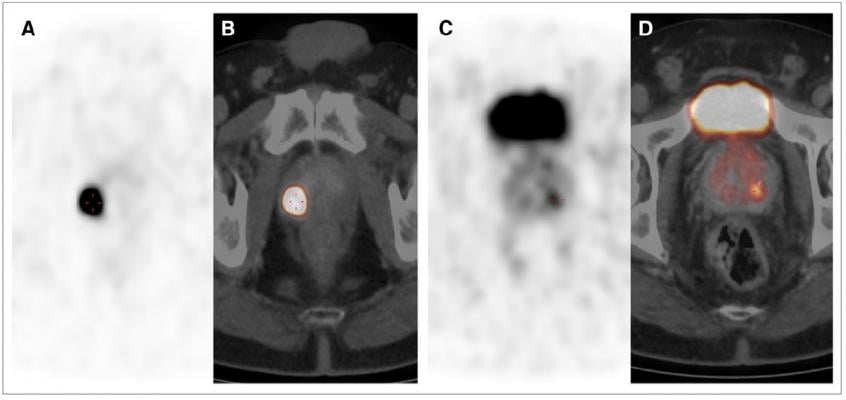

68Ga-PSMA PET/CT images showing multifocal PCA in peripheral zone with GS of 5 1 5 5 10. (A and C) Axial PET images. (B and D) Fused PET/CT images. SUVmax of lesion in B was 84.3 and that of lesion in D was 5.7. IRS was 3, and 80% of cells were stained. Credit: Senior author V Prasad, Charité Universitätsmedizin Berlin, Berlin, Germany.

The new study demonstrates that the maximum standardized uptake value (SUVmax) on Gallium-68 prostate specific membrane antigen (68Ga-PSMA) PET/CT scans correlates with PSMA-expression in primary prostate cancer. By this means, researchers were able to generate an SUVmax cutoff for the differentiation of cancerous and benign prostate tissue.

For the study, the data of 31 men (mean age of 67.2 years) who had undergone prostatectomies and preoperative PET scans were analyzed, with the SUVmax generated for suspicious areas and visually normal tissue. Both cancerous and benign prostate tissue samples (62 total) were stained with monoclonal anti-PSMA antibody. All the cancerous lesions could be confirmed histopathologically. The best cut-off value was determined to be 3.15 (sensitivity 97 percent, specificity 90 percent).

Prasad noted, “This validated cutoff of 3.15 for SUVmax enables the diagnosis of prostate cancer with a high sensitivity and specificity in both unifocal and multifocal disease.”